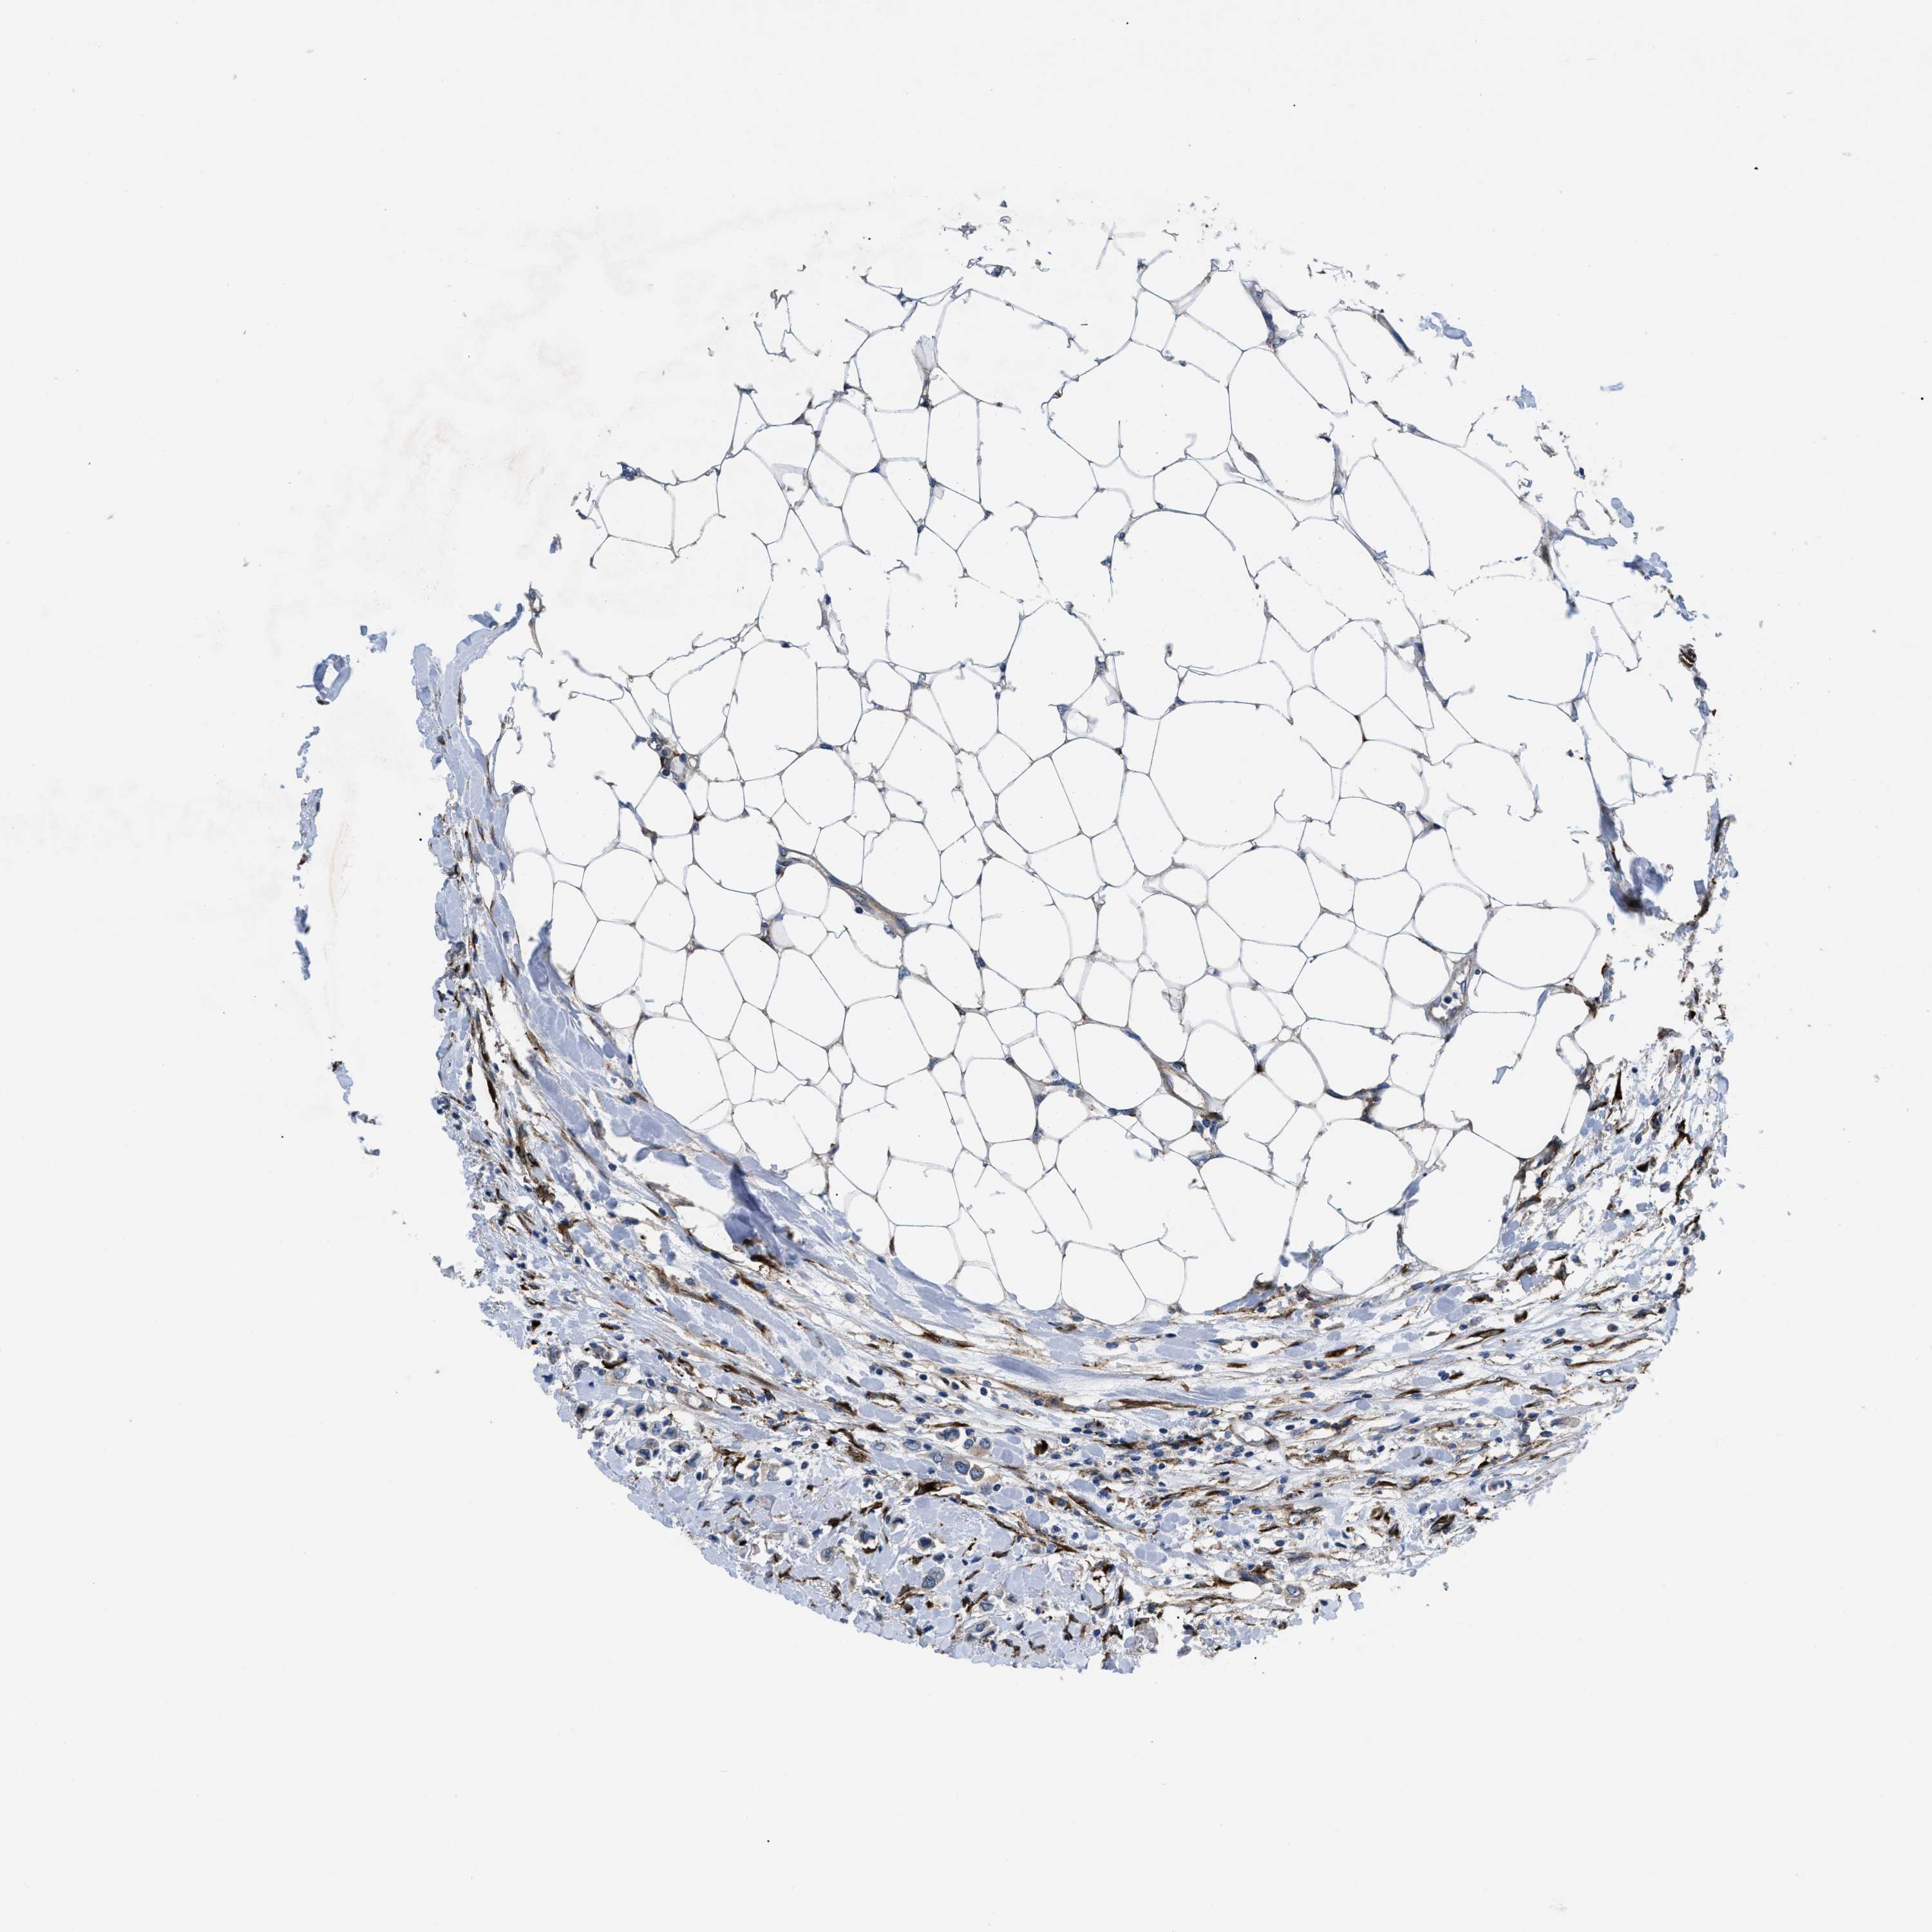

BRCA TCGA BRCA VALIDATION PROTEIN EXPRESSION